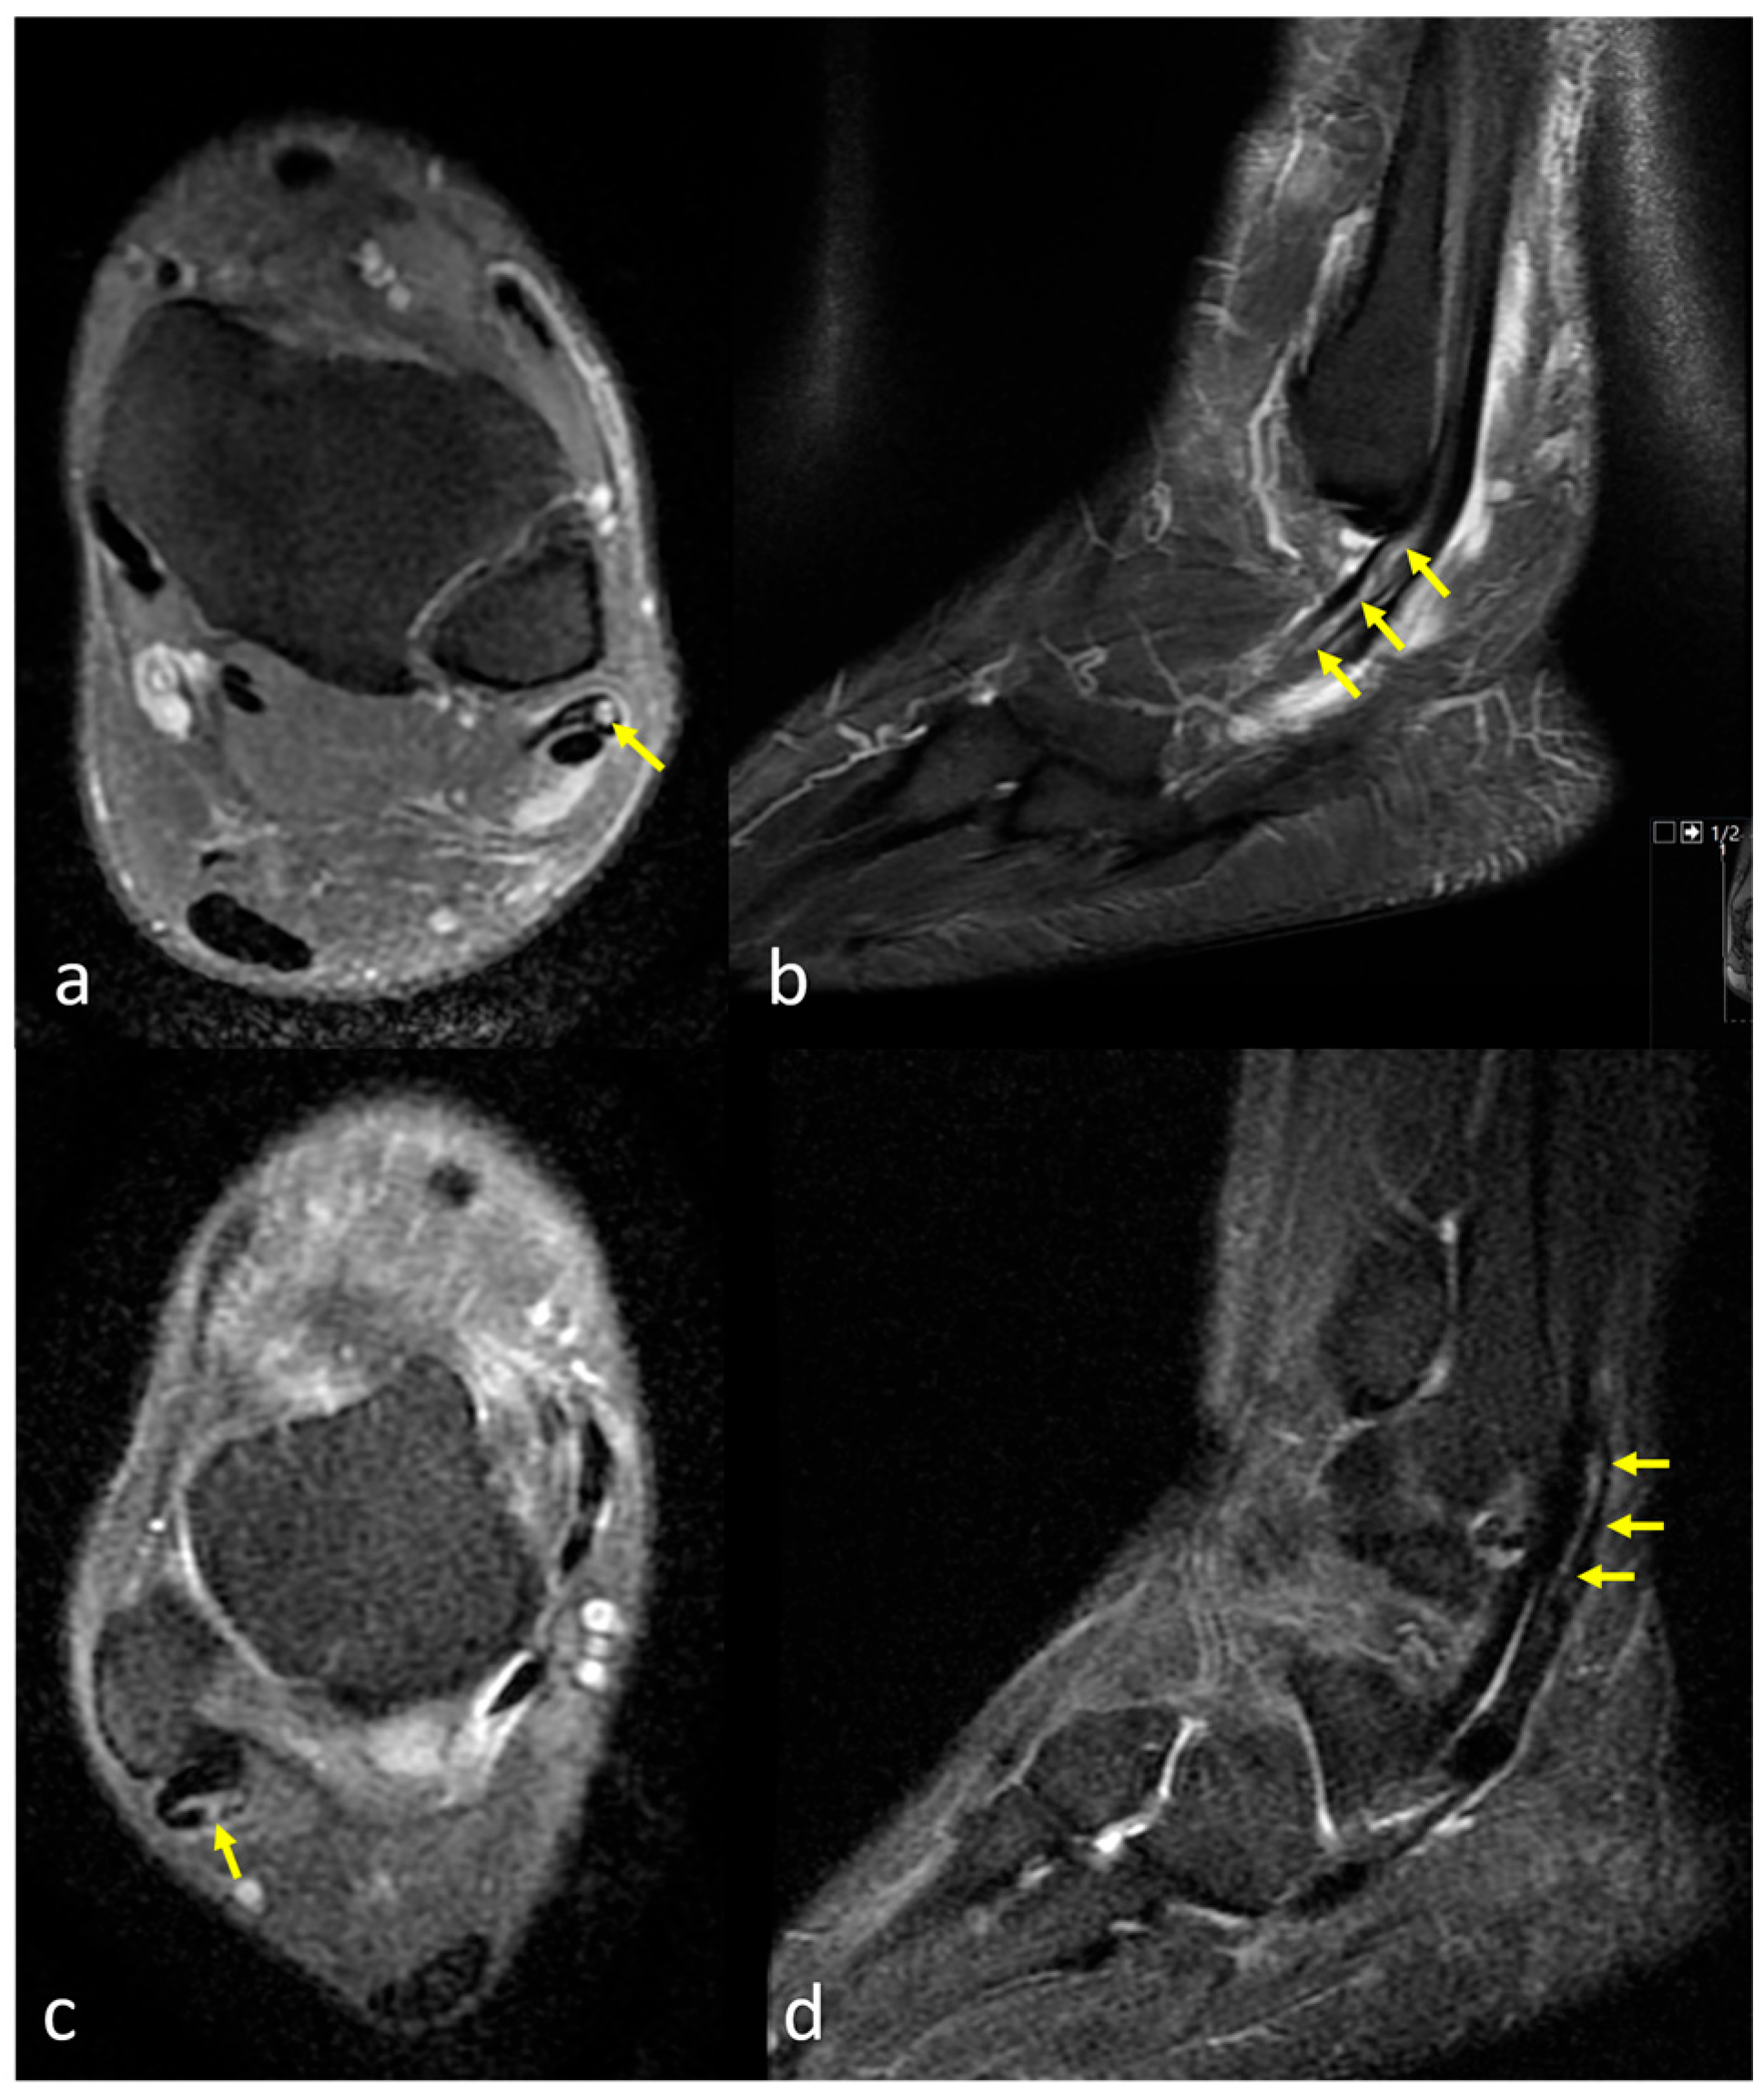

2.3. Assessment of the Peroneus Quartus Muscle and Peroneal Pathologies

2.4. Definitions of Peroneal Tendon Pathologies